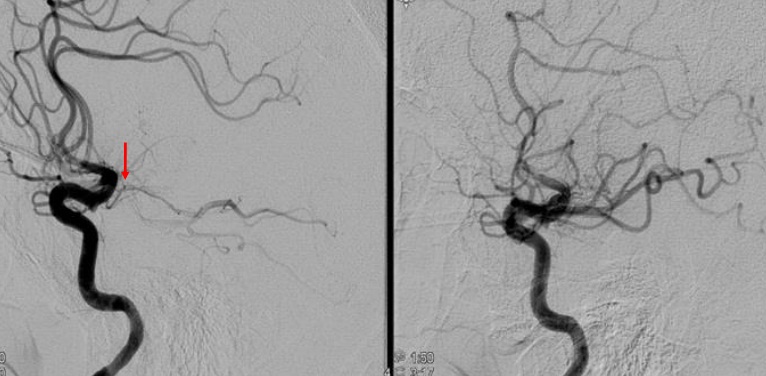

马上将患者送入导管室,目前发病才2个半小时,技术熟练的术者很快就下肢股动脉穿刺成功,随后术中看到左侧大脑中动脉被血栓堵住,操作过程中患者出现呼吸困难,氧饱和度下降,血压升高等变化,大家沉着应战,积极给予了应对措施,最终经过2个多小时惊心动魄的手术过程,最终取出了长长的血栓,解除了脑梗的“罪魁祸首”,血管再通,梗死区的脑细胞功能逐渐恢复。

左图显示大脑中动脉闭塞,右图显示取栓后血管再通